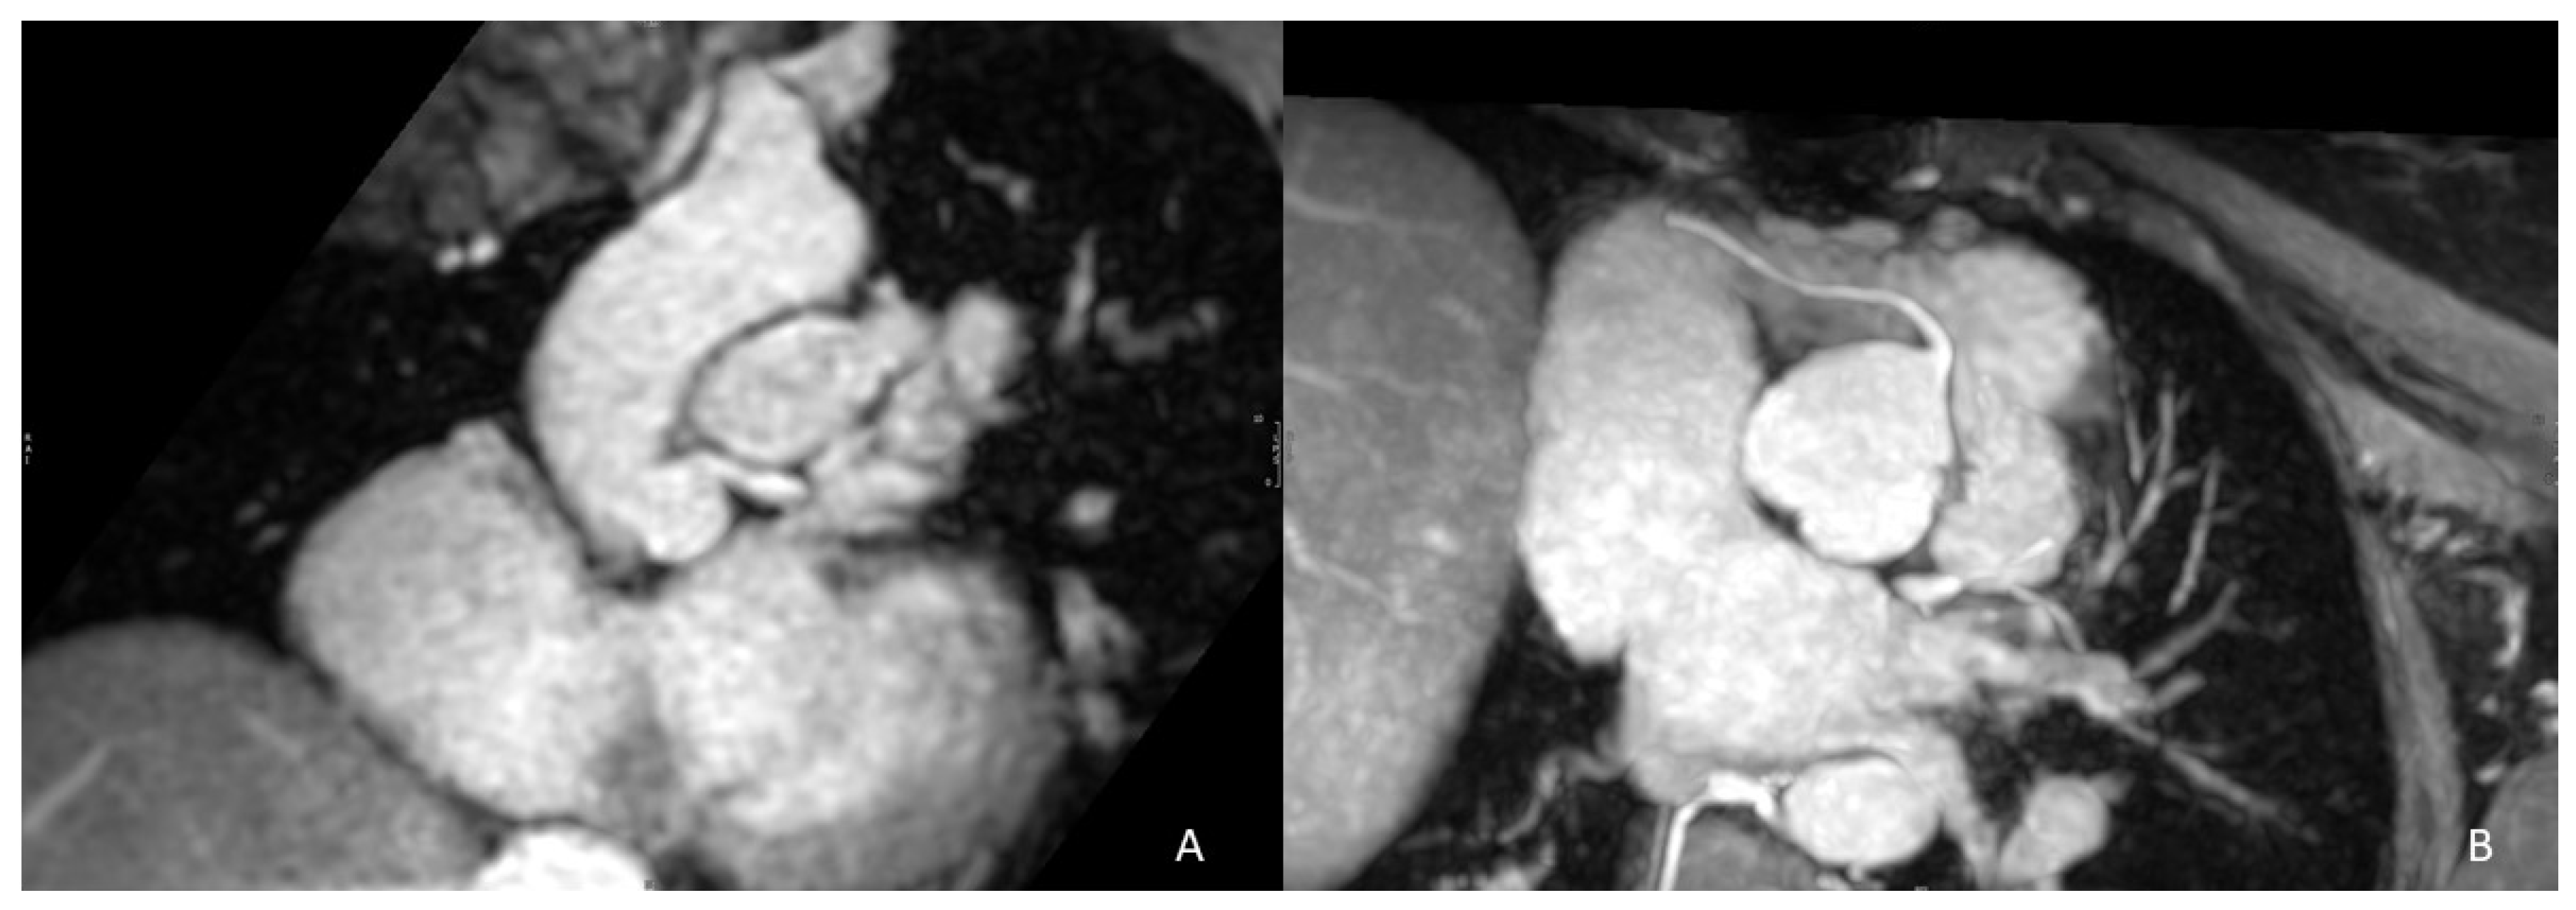

In addition to RVOT morphology and size, pre-procedural representation of the origin and course of the coronary arteries is fundamental to hypothesize potential coronary compression in the placement of the new valve, especially when this is planned to be oversized in comparison to the existing PV. The course of the left main and descending anterior coronary artery in proximity to the RVOT as well as a take-off angle ≤90° of the left main and right coronary arteries may increase the PPVI failure rate or even contraindicate it (Figure 2) [29]. Final invasive evaluation during cardiac catheterization is performed to cross-check data with a selective coronary angiography during balloon inflation in the RVOT to evaluate possible coronary compression during valve placement [30].

Figure 2.

Examples of an unfavorable coronary anatomy for PPVI. Extreme proximity of the left main coronary artery to the RVOT (<1 mm) has contraindicated percutaneous pulmonary intervention (A). (B) shows an acute take-off angle (<90°) of the proximal right coronary artery which is an issue for successful PPVI.